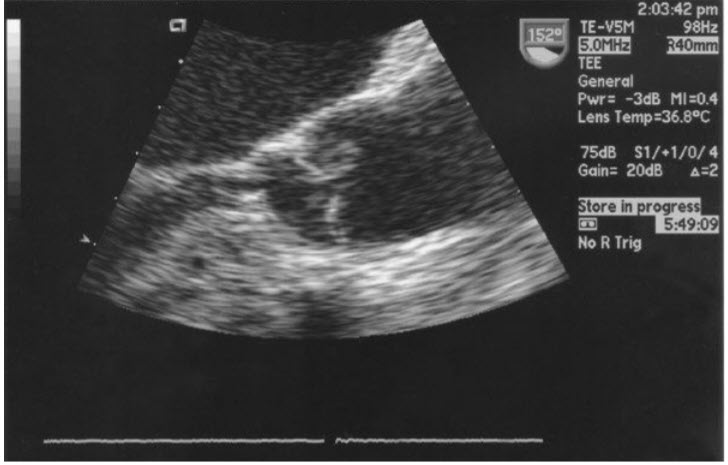

Figure b. A magnified TEE long-axis view of the LVOT, aortic valve, and ascending aorta. There is a membrane visible in the LVOT, consistent with a subaortic membrane.